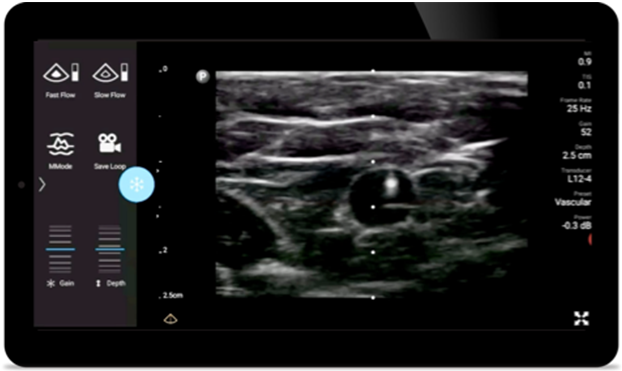

Mniej powikłań podczas zabiegów z wprowadzeniem igły

Przenośny system Lumify do stosowania w anestezjologii pomaga wyraźnie uwidocznić granice tkanek, otaczające je nerwy, naczynia oraz powierzchnie powięzi podczas wprowadzania igły.

System Lumify pomaga wyraźnie zwizualizować wprowadzaną igłę, otaczające ją nerwy, naczynia oraz powierzchnie powięzi.